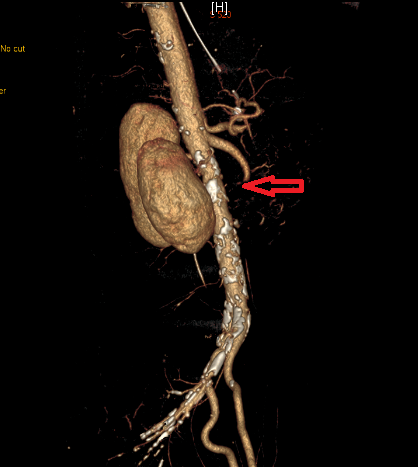

红色箭头处见本应延续的肠系膜上动脉中断

急性肠系膜缺血是一种罕见的急腹症,急诊发病率占0.09-0.2%,但死亡率高于脑卒中,高达50-80%。事不宜迟,赵宏伟医师立即启动了我院的肠卒中绿色通道,马上为患者进行了术前的常规化验及腹部血管CTA检查。结果显示患者为肠系膜上动脉栓塞,D二聚体也升高到了3.72mg/L,血气分析显示患者为代谢性酸中毒,乳酸高达5.4mmol/L。按照绿色通道流程,血管外科赵俊来医师与急诊外科赵宏伟医师共同为患者制定了手术方案,尽快绝急手术。患者自来院不到2小时,就进入了手术室进行手术。